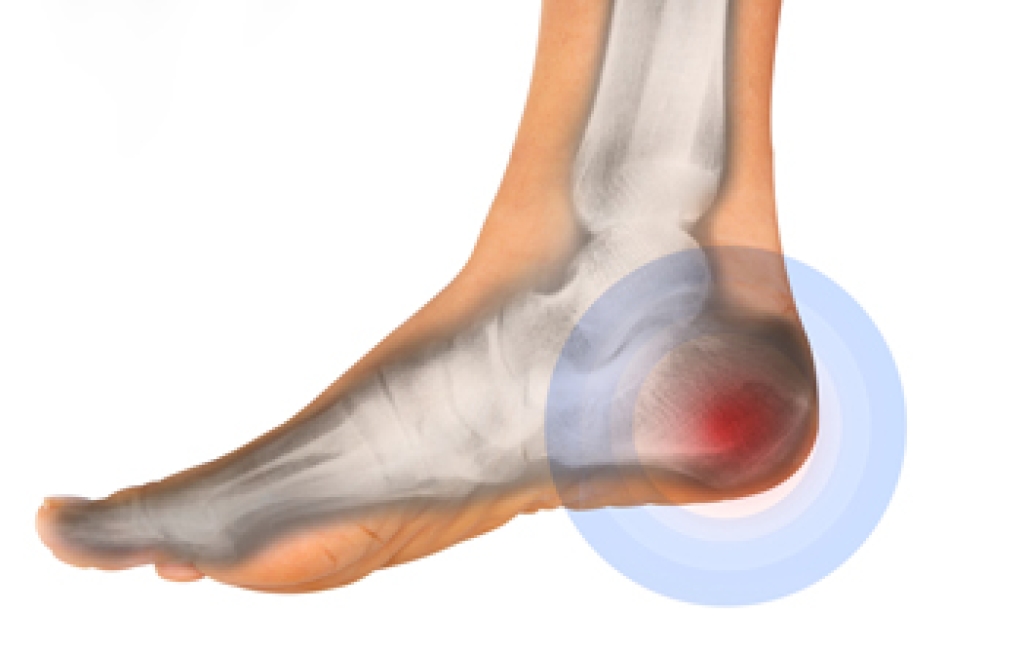

What Is Heel Spur Syndrome?

Heel spur syndrome is a painful condition where a small bony growth forms under the heel. This often develops with plantar fasciitis, which is irritation of the thick band of tissue supporting the arch of the foot. Those with this condition usually feel sharp pain when taking their first steps in the morning. Most people improve with rest, stretching, shoe changes, or targeted exercises. When these options do not work, a minimally invasive surgical method may be considered. This procedure uses a small cut on the bottom of the foot to release tight tissue and reduce pressure. Research shows that this procedure can provide strong pain relief and fast healing for many people. Recovery is typically quicker than traditional surgery, helping people return to daily activities with less discomfort. If you have heel pain, it is suggested that you see a podiatrist for a proper diagnosis and treatment that is right for you.

Heel spurs are formed by calcium deposits on the back of the foot where the heel is. This can also be caused by small fragments of bone breaking off one section of the foot, attaching onto the back of the foot. Heel spurs can also be bone growth on the back of the foot and may grow in the direction of the arch of the foot.

Older individuals usually suffer from heel spurs and pain sometimes intensifies with age. One of the main condition's spurs are related to is plantar fasciitis.

Pain

The pain associated with spurs is often because of weight placed on the feet. When someone is walking, their entire weight is concentrated on the feet. Bone spurs then have the tendency to affect other bones and tissues around the foot. As the pain continues, the feet will become tender and sensitive over time.